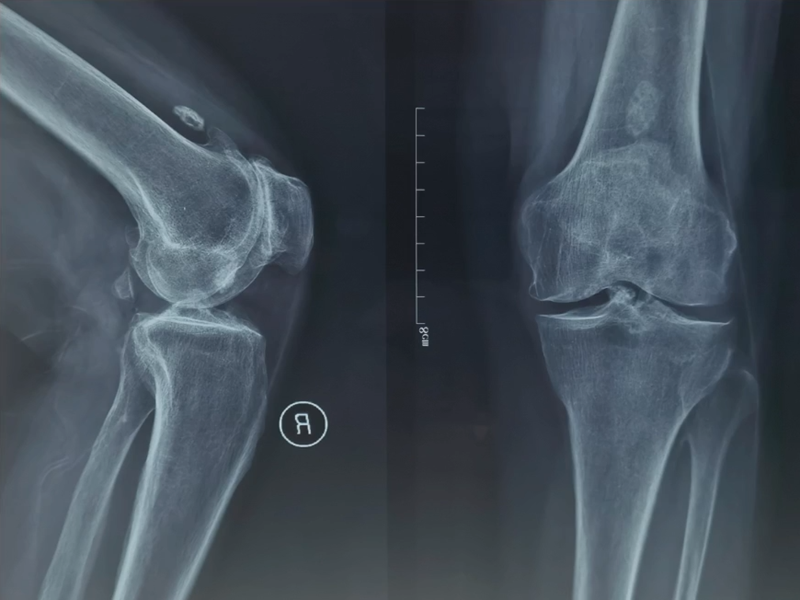

术前X线片显示:正位片胫骨关节间隙良好,轻度骨质增生。侧位片可见髌骨与股骨外髁形成骨磨骨状态,髌上囊有游离体,骨赘产生。

术前X线